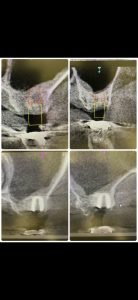

次は、インプラント定期検診

安定!💪

画像見れば変遷がなんとなくわかる

詳細は割愛

患者さんの、Q OLを下げない為に色々試行錯誤してます